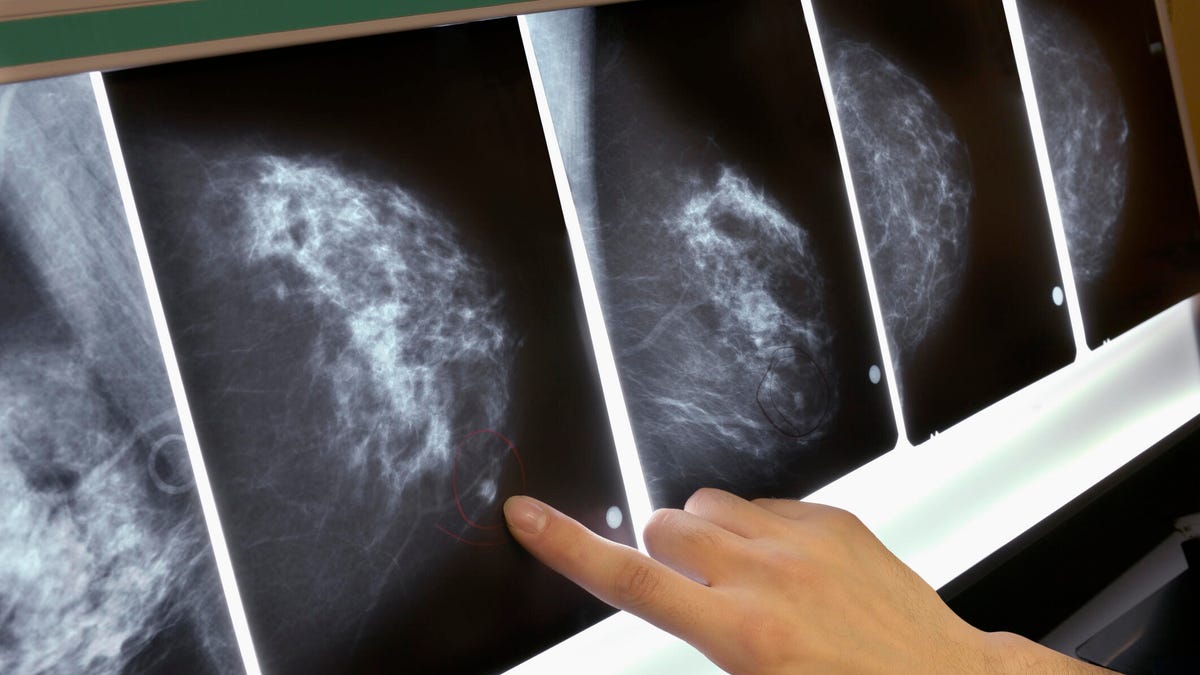

Unfortunately the current primary method of detection via mammogram -- a scan of the breast that's then examined by a radiologist -- can result in a false diagnosis of cancer for many women. For others, it misses the cancer altogether.

In the paper, researchers detail the successful results of an AI model able to identify breast cancer in mammograms missed by radiologists when tested against scans of over 25,000 women from the UK and over 3,000 women from the US. The AI, which was trained on anonymized mammograms, was also able to reduce the number of false diagnoses of breast cancer in healthy women.

Mammography is the most common tool used to diagnose cancer, but radiologists miss one in five breast cancers. On the flip side, 50% of women who attend screenings over the course of 10 years in the US will receive a false diagnosis.